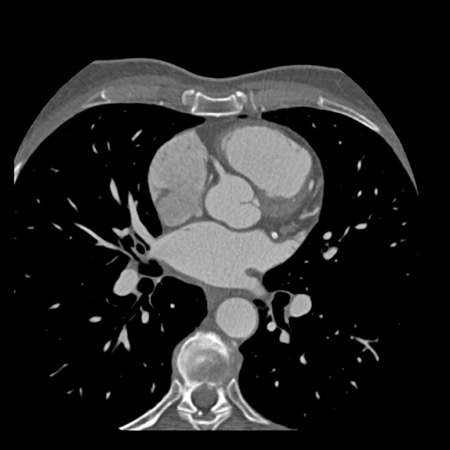

Modifier S – stent

The presence of a stent is indicated by modifier “S”.

Examples

- If a patient has a stent, showing no in-stent restenosis and a mild

(25-49%) stenosis in the coronaries, this patient classifies as CAD-RADS

2/S. - Similarly, a patient with no in-stent restenosis but severe (70-99%)

stenosis in a coronary other than LM classifies as CAD-RADS 4A/S. - If there is a severe (70-99%) in-stent restenosis in a coronary other

than LM, this patient classifies as CAD-RADS 4A/S. - If the stent is non-diagnostic and there is no >49% stenosis present

in the coronaries, the patient classifies as CAD-RADS N/S.

Note: the location of the stenosis does not matter, when using

CAD-RADS.

What matters is that the patient has a severe stenosis and needs further

management.

Please note: total coronary plaque burden should also be added and is

placed before the modifier S.